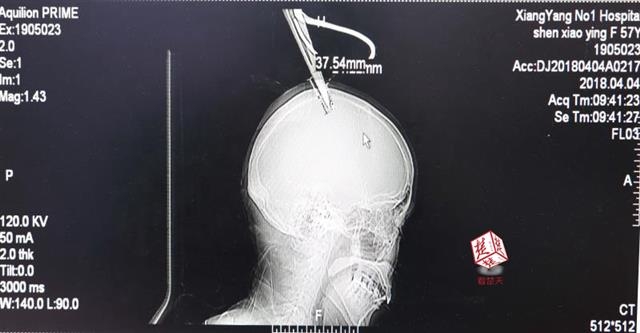

女子顱骨插進(jìn)剪刀 不慌不忙坐公交車就醫(yī)

醫(yī)生檢查發(fā)現(xiàn),剪刀刀尖斜嵌在沈某顱骨里,離腦髓只有兩三毫米。所幸是斜著插進(jìn)去,如果是垂直刺入,很有可能造成癱瘓。

4月4日清晨,襄陽(yáng)市樊城區(qū)太平店鎮(zhèn)57歲的農(nóng)村婦女沈某,在采摘香椿嫩芽時(shí),綁在竹桿上的剪刀因竹子腐朽不慎折斷,剪刀斜插入頭顱。經(jīng)過(guò)及時(shí)搶救,目前脫離生命危險(xiǎn)。

“當(dāng)時(shí)感覺還好,就是頭有點(diǎn)木?!鄙蚰痴f(shuō),由于自己感覺沒(méi)什么大礙,便沒(méi)坐120急救車,而是和家人一起坐了一個(gè)小時(shí)的公交車趕到市區(qū)醫(yī)院。

醫(yī)生檢查發(fā)現(xiàn),剪刀刀尖斜嵌在沈某顱骨里,離腦髓只有兩三毫米。所幸是斜著插進(jìn)去,如果是垂直刺入,很有可能造成癱瘓。最終經(jīng)過(guò)手術(shù),剪刀被取出,沈某目前仍在ICU進(jìn)一步觀察。